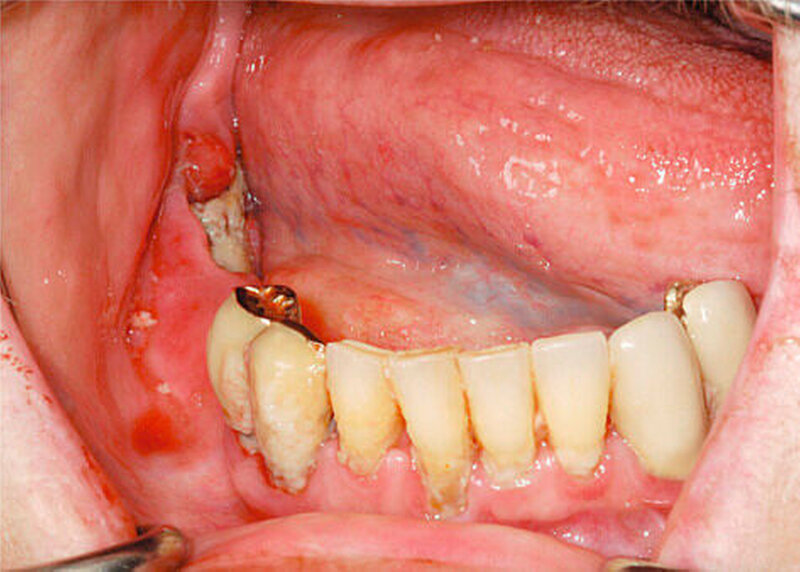

Neben den bekannten Bisphosphonaten werden zunehmend Fälle von Kiefernekrosen auch durch Denosumab, einen RANKL-Antagonisten, beobachtet. Deswegen sollte speziell auch nach den Medikamenten Prolia©und XGeva©vor oralchirurgischen Eingriffen gefragt werden. Während Prolia©in der Osteoporosetherapie Anwendung findet, wird XGeva©bei Prostata- und Mammakarzinompatienten subkutan verabreicht und hat speziell auch bei Nierenfunktionsstörungen seine Indikationen. Die Halbwertszeit von Bisphosphonaten beträgt bis zu zehn Jahren, die von Denosumab in der Regel zwischen 80 und 120 Tagen [Ruggiero, 2013]. In direkten Vergleichsstudien bei onkologischen Patienten werden etwas mehr gehäuft Nekrosen durch Denosumab als durch Zoledronat (Aminobisphosphonat) festgestellt. Die Erfolge einer definitiven Heilung waren jedoch bei den Denosumabnekrosen scheinbar besser [Saad et al., 2012; Van Wyngaert et al., 2011]. Als Hauptursachen einer Kiefernekrose sind bei beiden Präparaten nach wie vor Zahnextraktionen zu nennen. Das zweitgrößte Risiko durch Prothesendruckstellen wird jedoch häufig unterschätzt (Abbildungen 5 und 6) [Hoefert, 2012].

Trotz des Zeitraums von aktuell elf Jahren, in denen Kiefernekrosen bekannt sind (Erstbeschreibung 2003 durch Marx), ist die Ätiologie weiterhin ungeklärt. Zunehmend rückt die Bedeutung einer Infektion in Ätiologie und Therapie der Kiefernekrosen in den Mittelpunkt [Kumar et al., 2010; Pazinas, 2011]. Durch eine adäquate Antibiotikatherapie können nicht nur die Klinik und das Erscheinungsbild der Nekrose gebessert und in der Regel eine Schmerzfreiheit erreicht werden, sondern es werden auch bessere Erfolge bei der operativen Therapie verzeichnet [Hoefert und Eufinger, 2011]. Tendenzen zeichnen sich auch ab, dass eine frühzeitigere operative Therapie bei Bisphosphonatnekrosen empfohlen werden kann, um eine dauerhafte Heilung zu erzielen. Eine Heilung in diesem Sinne beschreibt eine dichte Schleimhaut ohne Hinweise auf freiliegende Knochenareale oder Fistelungen bis zum Knochen [Lesclous et al., 2013; Graziani et al., 2012; Hoefert und Eufinger, 2011].